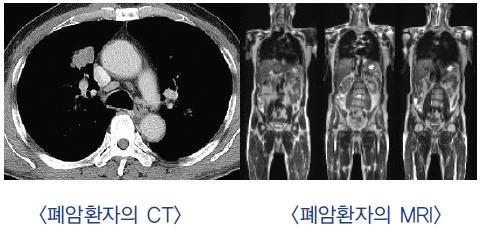

이러한 폐암의 원인으로 인해 폐암으로 진단되기 전에 폐암 초기증상을 조기에 발견하면 다른 장기로의 전이나 진행성 폐암으로의 진행을 어느 정도 지연시키거나 적절하게 치료할 수 있지만 일반적으로 폐암의 초기 단계는 특별한 징후나 증상이 없으므로 조기에 발견하는 경우는 극히 드뭅니다.